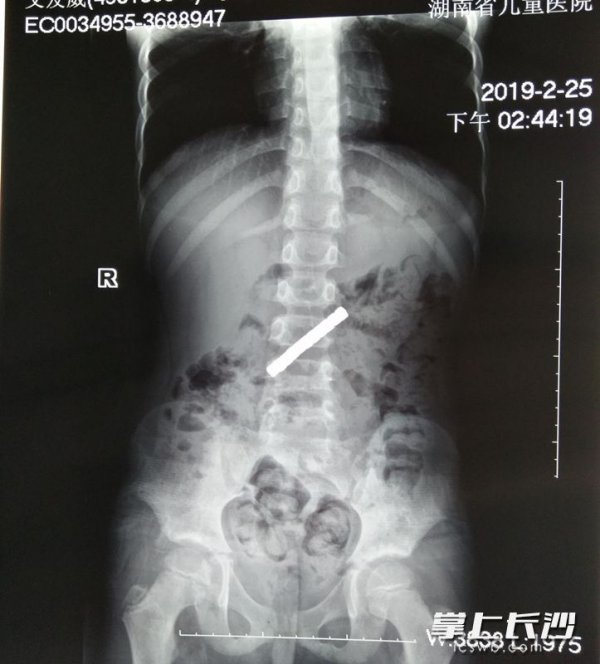

衡东有个7岁男孩叫康康,是化名,他在一家售卖文具的店铺购买了一包正方形的强力磁铁,玩耍时,这个孩子因为好奇,一次性吞下了11块强力磁铁,康康的母亲向记者透露kaiyun全站网页版登录,康康是个喜欢摆弄东西,好奇心旺盛的孩子,经常把各种物件往嘴里塞,尽管这位母亲时常告诫和引导,却未曾料到他会吞食如此多的磁铁。二月份二十四日,康康在本地医疗机构接受检查,查明磁铁已进入消化道内部,并且无法借助胃镜将其移除,康康因此产生了反胃、腹部疼痛的不适反应。第二天,康康跟随父母前往湖南省儿童医院普外一科,该科室的医疗小组在25日夜间紧急为康康实施手术,手术中发现康康胃部有6块磁铁,其余5块磁铁则位于小肠内,强大的磁力导致胃与小肠相互吸引并产生粘连,进而引发肠梗阻,手术过程中医生成功取出通过x光检测到的全部11块磁铁,检查还发现胃与小肠存在多处破损,随即进行了相应的修补手术,目前康康的身体状况已经趋于稳定。

该院普外一科主治医师张甜表示:磁铁具备特殊性质,不同于其他杂物,在消化道内,它们会彼此吸引,形成串状或块状kaiyun官方网站登录入口,同一段肠道以及不同肠段的磁铁也会相互吸引,尤其是位置相距较远的磁铁相互吸引时,会压迫肠道,导致肠管堵塞、肠道损伤。这种情况磁铁无法自行从身体内排出,必须借助手术将其取出。